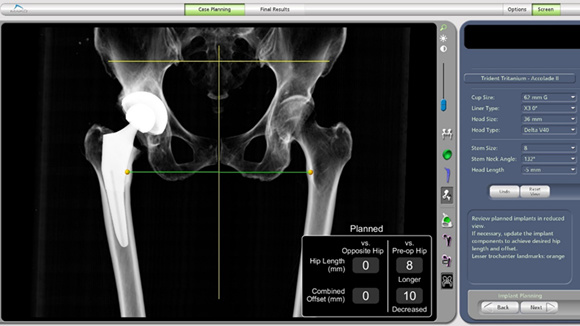

机器人系统中显示的患者术前的影像学资料(其中患侧腿较健侧腿短缩8mm)

经机器人系统模拟的假体植入后的影像学结果(患侧腿恢复长度,与健侧完全等长)